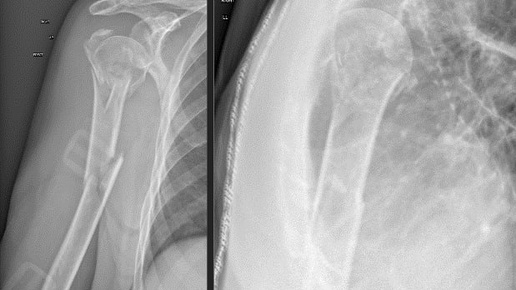

🏥 Консервативное лечение переломов плечевой кости у пожилых пациентов В отделение экстренной помощи Ильинской больницы обратилась пациентка 80 лет. Со слов пациентки и сопровождающих, травма получена в быту: падение на правый бок в результате головокружения. Почувствовала резкую боль, ограничение функции правой верхней конечности. В отделении экстренной помощи Ильинской больницы выполнена рентгенография правого плеча, по результатам которой выявлен сложный оскольчатый перелом хирургической шейки с отрывом большого бугорка, а также диафизарный перелом плечевой кости со смещением...